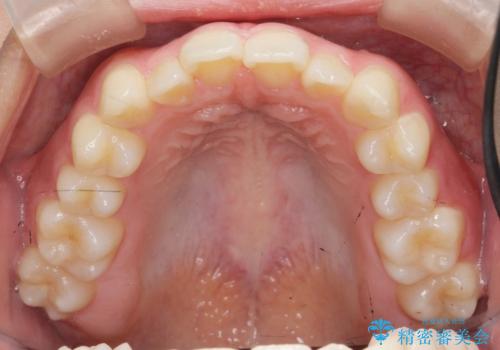

マウスピース矯正で前歯のガタつきを改善

- 上下の前歯のガタつきの改善を求めて、矯正治療を希望され来院されました。

矯正検査の結果、マウスピース矯正システム インビザラインの適応であることからワイヤーを用いず矯正治療を進めることとしました。

1日20時間以上の使用時間をきっちりと守っていただけたため、良好な治療結果、歯並びを手に入れることができました。